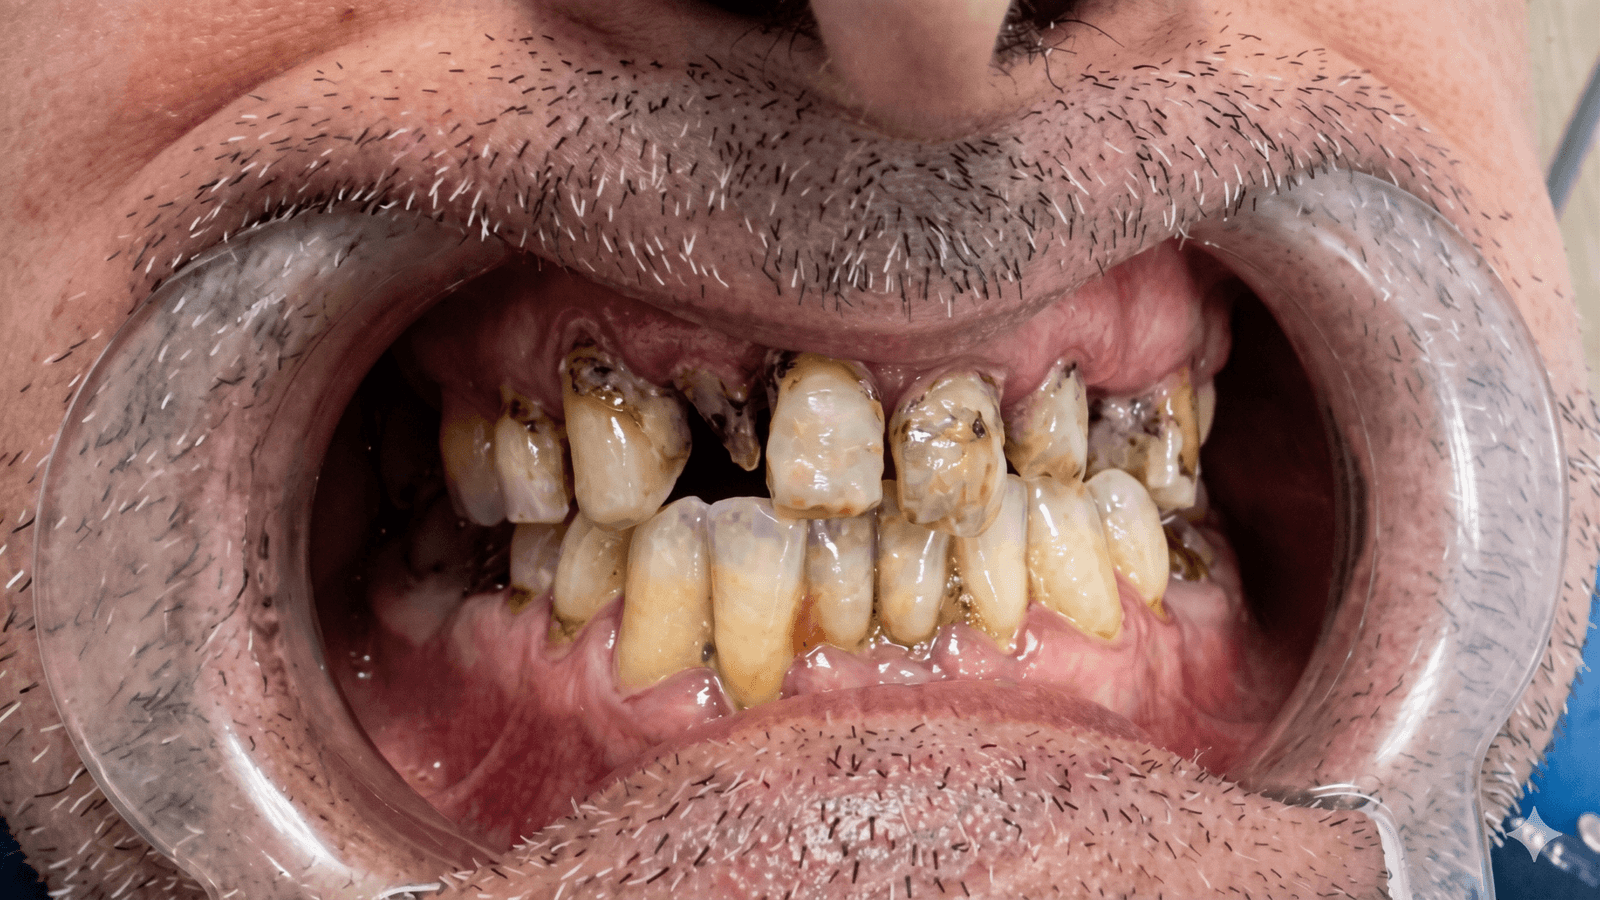

Avevo perso quasi tutti i denti dell'arcata superiore e in Italia mi avevano chiesto 24.000€ per un All-on-6. A Tirana ho fatto lo stesso lavoro a 9.500€, con impianti Nobel Biocare e protesi definitiva in zirconia. Il dentista ha studiato in Germania, parlava italiano, era preparatissimo. Sono passato in due viaggi di 4 giorni e ora mangio di nuovo come prima.

Stefano V.

Padova • Impianti All-on-6